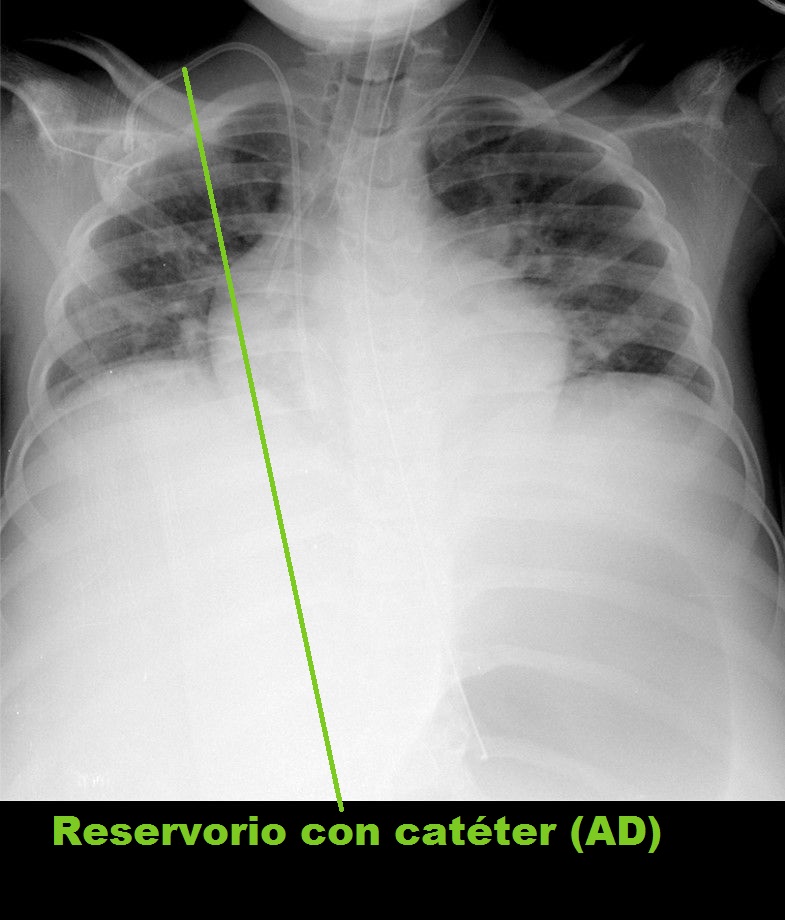

Los catéteres venosos centrales, ya sean de inserción central o periférica, deben quedar con sus extremos también próximos a la unión de la vena cava superior (VCS) con la AD.

• Reservorio con catéter (AD)